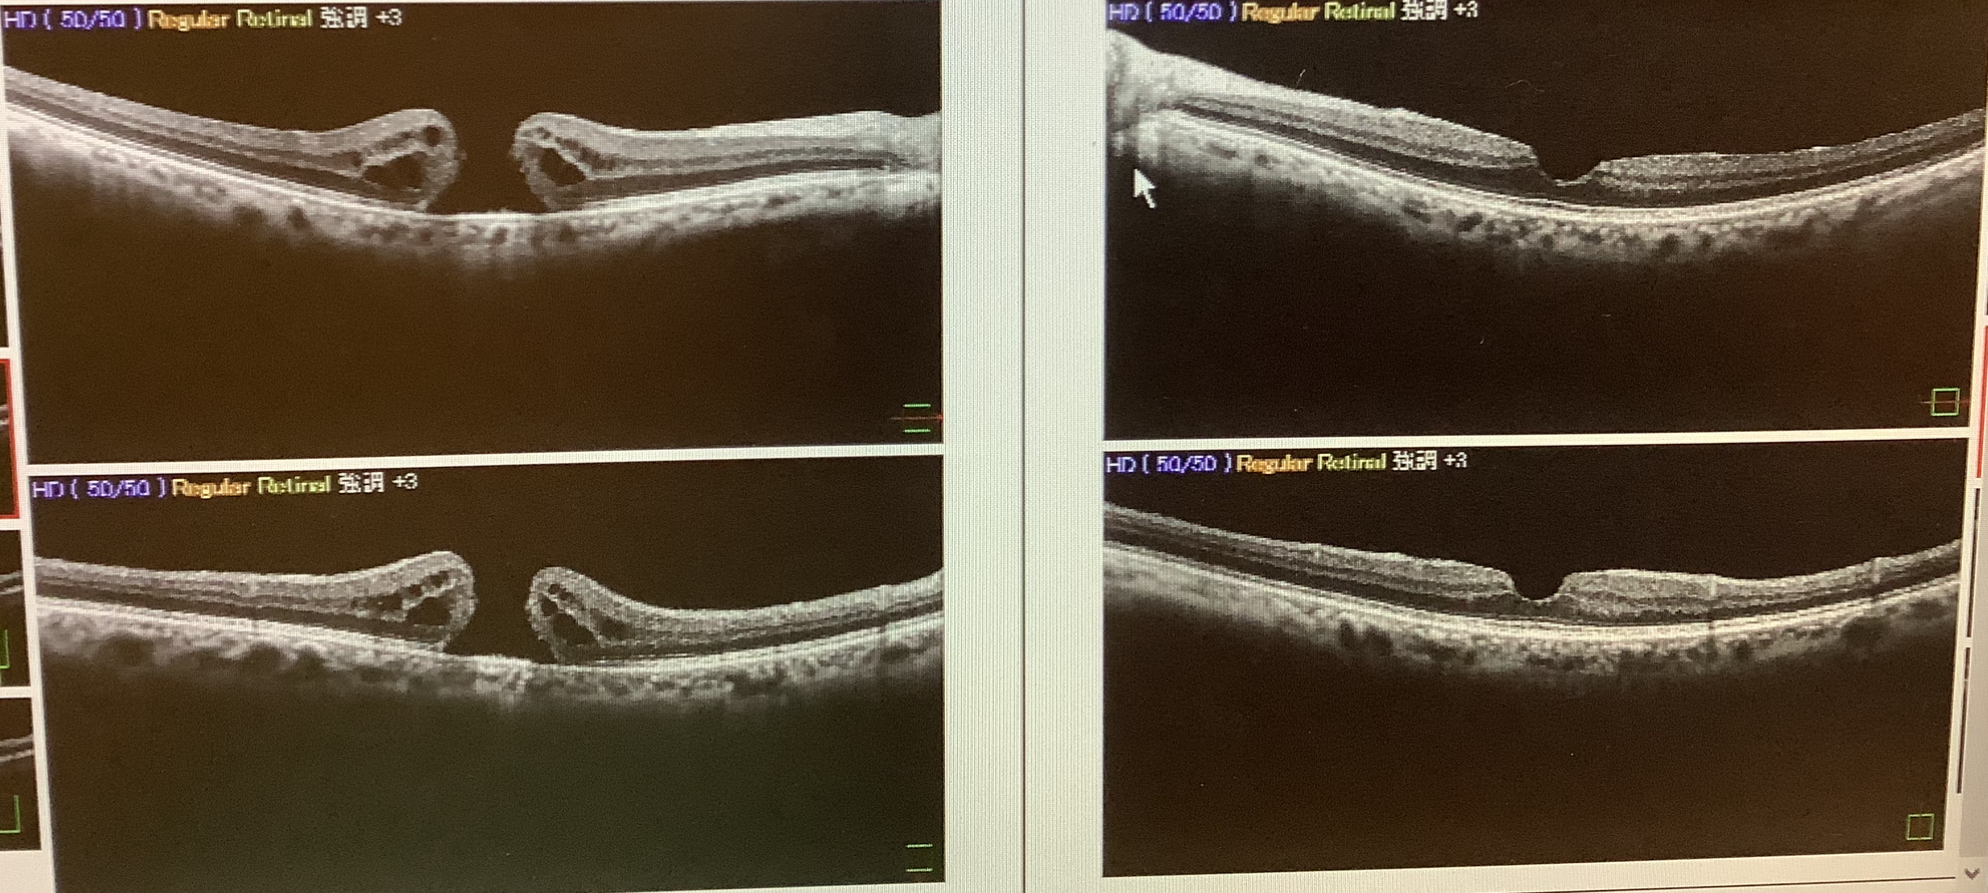

“黄斑円孔”とは網膜の中心部の大事な部分である黄斑に丸い穴があいてしまった状態ですが、症状としては歪みや中心部の暗さ(中心暗点)が現れます。この患者さまは70代の男性でしたが、問診票には『右眼の白内障の手術希望』と記入し受診されていました。もちろん、年齢的に白内障も存在しますが、白内障の程度は左右同じくらいにもかかわらず、視力は左は1.2と良好ですが、右は0.4まででした。よくよく話を聞くと、ここ数週間でどんどん見えにくくなってきたため、娘さんに勧められて早めに受診したそうです。白内障は手術の時期が遅くともきれいに手術ができれば、問題なく視力は改善が得られます。しかし、この患者さまのように網膜の病気はタイミングが遅くなると、十分な改善が難しくなってしまうことも多く、黄斑円孔も早めの手術が望ましいため、来週、準緊急で手術を予定させていただきました。

↑OCT検査 右眼(向かって左側)が黄斑円孔です。